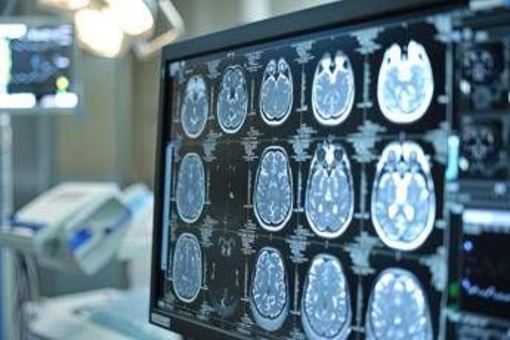

"Sono tumori cerebrali molto complessi e che spesso vengono diagnosticati in età giovanile - afferma Saverio Cinieri, presidente di Fondazione Aiom - Si sviluppano da cellule del cervello chiamate gliali e possono avere una prognosi variabile, ma potenzialmente a lungo termine. La gestione della patologia richiede una stretta collaborazione fra neurochirurgo, radioterapista e oncologo medico. Attraverso il bisturi è possibile rescindere la massa tumorale oppure eseguire una biopsia grazie a nuove e sofisticate tecnologie. La radioterapia permette di ridurre il rischio di recidiva o eliminare quella parte di cancro che non è stato possibile rimuovere chirurgicamente. Viene somministrata insieme alla chemioterapia e le sedute sono di solito diluite nel corso del tempo, per limitare l'impatto degli effetti collaterali. Infine, l'oncologo medico deve scegliere i farmaci da somministrare e deve selezionarli valutando le condizioni cliniche del singolo paziente".

"Anche per il trattamento dei gliomi, in particolare quelli di basso grado, si può ricorrere all'oncologia di precisione che potrà ridisegnare la pratica clinica nel prossimo futuro - illustra Enrico Franceschi, direttore dell'Oncologia del sistema nervoso all'Irccs Istituto delle scienze neurologiche di Bologna - E' molto importante verificare la presenza o meno delle mutazioni Idh1 e Idh2. Questi biomarcatori indicano specifiche patologie caratterizzate da una prognosi decisamente più favorevole e maggiore sensibilità dei gliomi alla radio e chemioterapia. Al momento della diagnosi è quindi essenziale l'esecuzione precoce di alcuni test molecolari per identificare al meglio i diversi sottotipi di gliomi. Tra le terapie di nuova generazione vi è anche vorasidenib, un farmaco orale inibitore Idh1 e Idh2 che ha dimostrato di essere un trattamento efficace nel posticipare la radio e chemioterapia nei gliomi di basso grado ed è una rilevante innovazione medico-scientifica".

"Ancora una volta l'oncologia medica è centrale nella gestione multidisciplinare di neoplasie estremamente complesse ed insidiose - sottolinea Franceschi - Il trattamento dei gliomi inizia nel momento della diagnosi che deve essere sia morfologica che molecolare. Esistono infatti 150 diversi sottotipi di neoplasia cerebrale ed è fondamentale riconoscere fin da subito le caratteristiche del singolo caso per poter così selezionare le terapie più appropriate. Fino a pochi anni fa avevamo a disposizione solo chirurgia, radioterapia e chemioterapia. Ora i farmaci ad azione mirata sono una realtà anche nella cura dei tumori cerebrali che esprimano specifiche alterazioni molecolari".